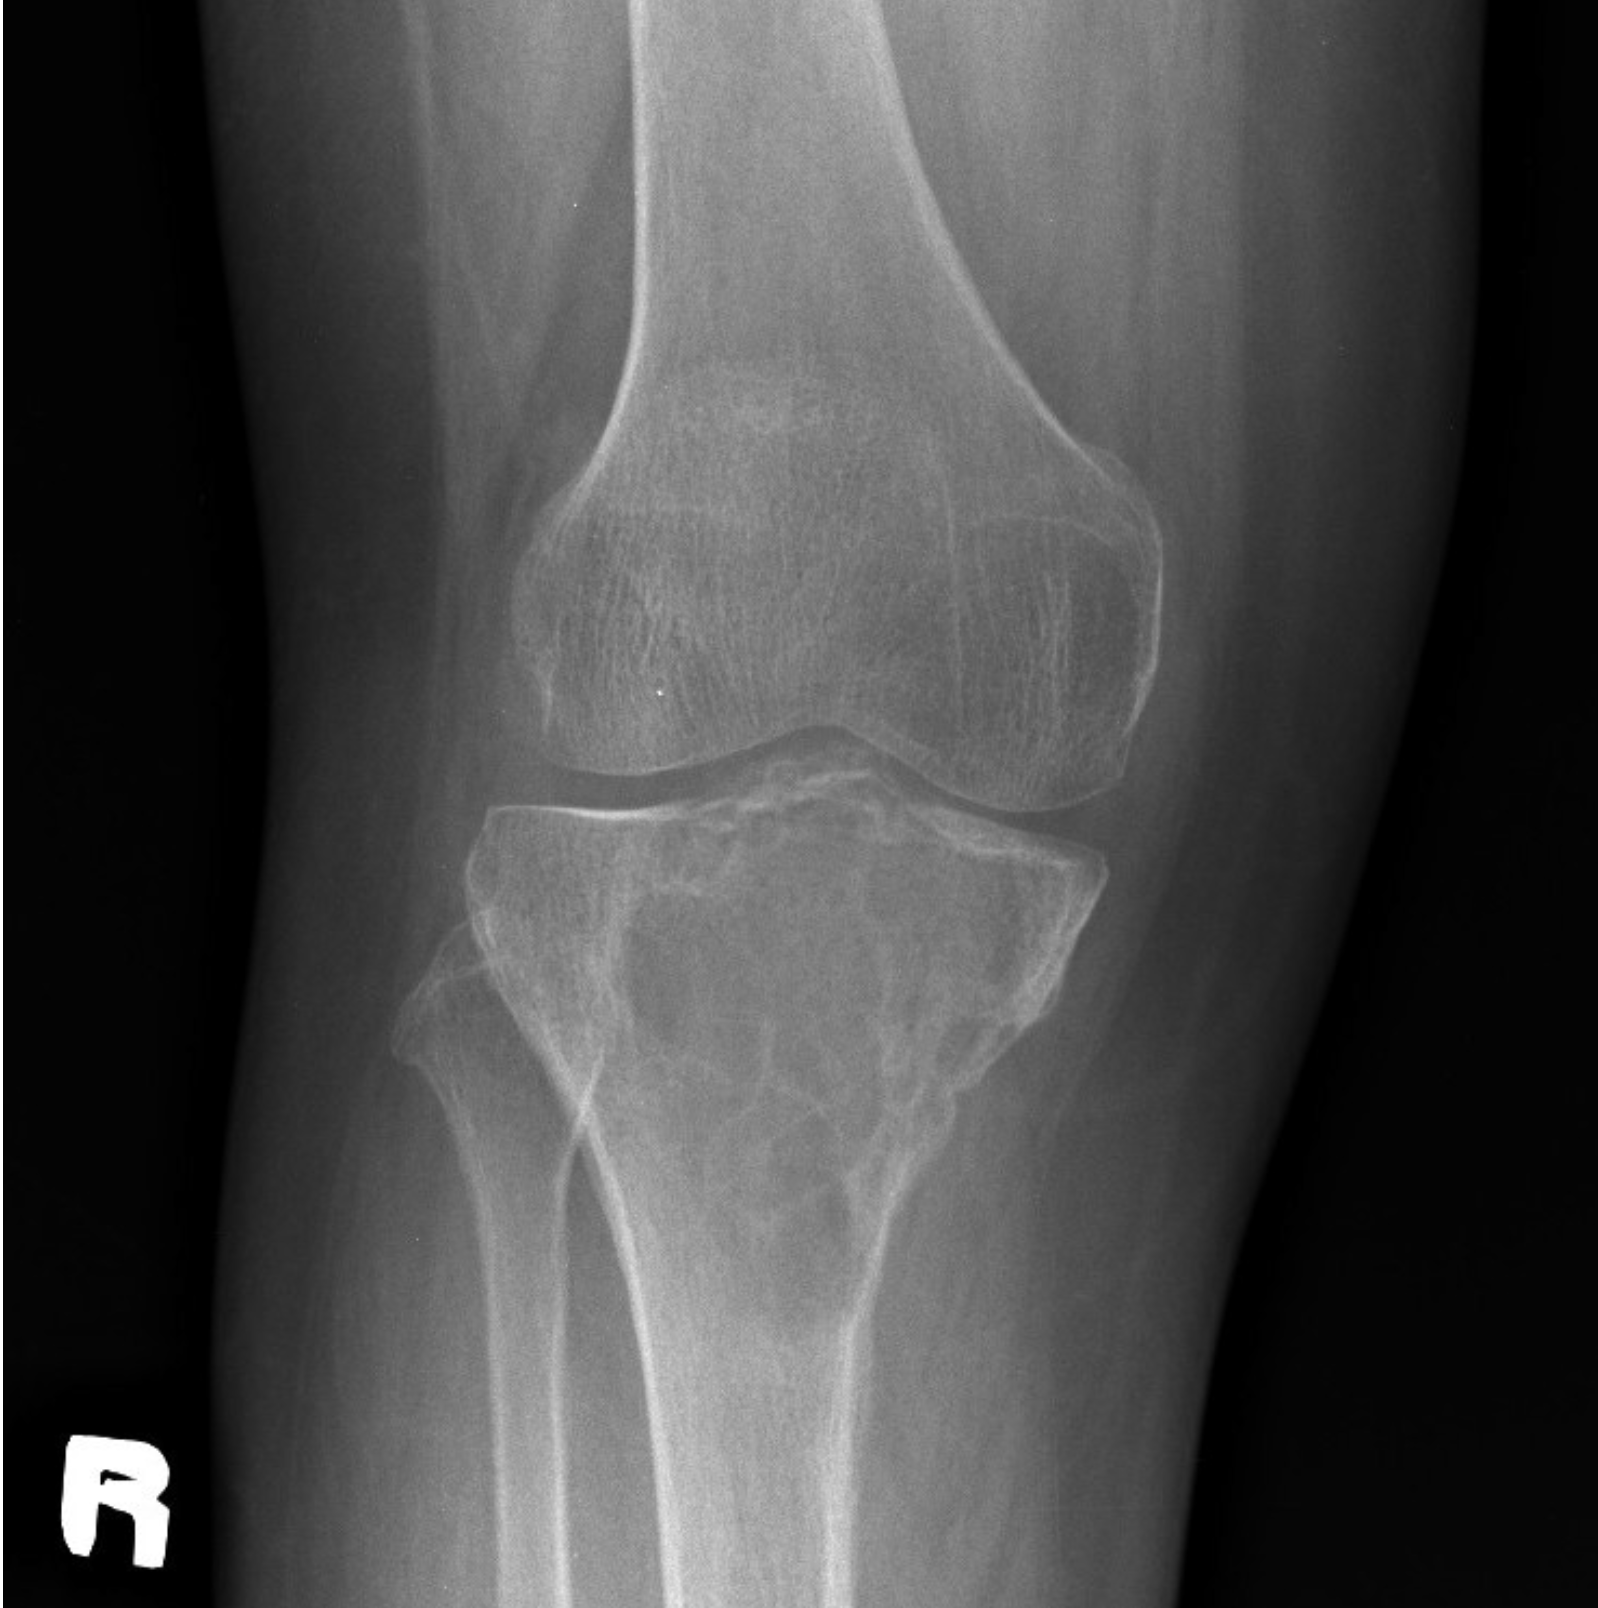

Right knee radiograph in frontal projection: A well-defined minimally expansile solitary lytic lesion in the meta-epiphysis of proximal tibia, with multiple internal trabeculations/septations (“soap-bubble” appearance). It has a narrow zone of transition with minimal marginal sclerosis. It is eccentric in location, extends to the subarticular region, with thinning of the overlying cortex. No cortical break. Minimal periosteal reaction at the inferomedial cortex of the proximal diaphysis.

*Image retrieved from PACS USM Workflow Manager

- Image description by Dr Fattah Rahiman Ghazali (Radiologist)